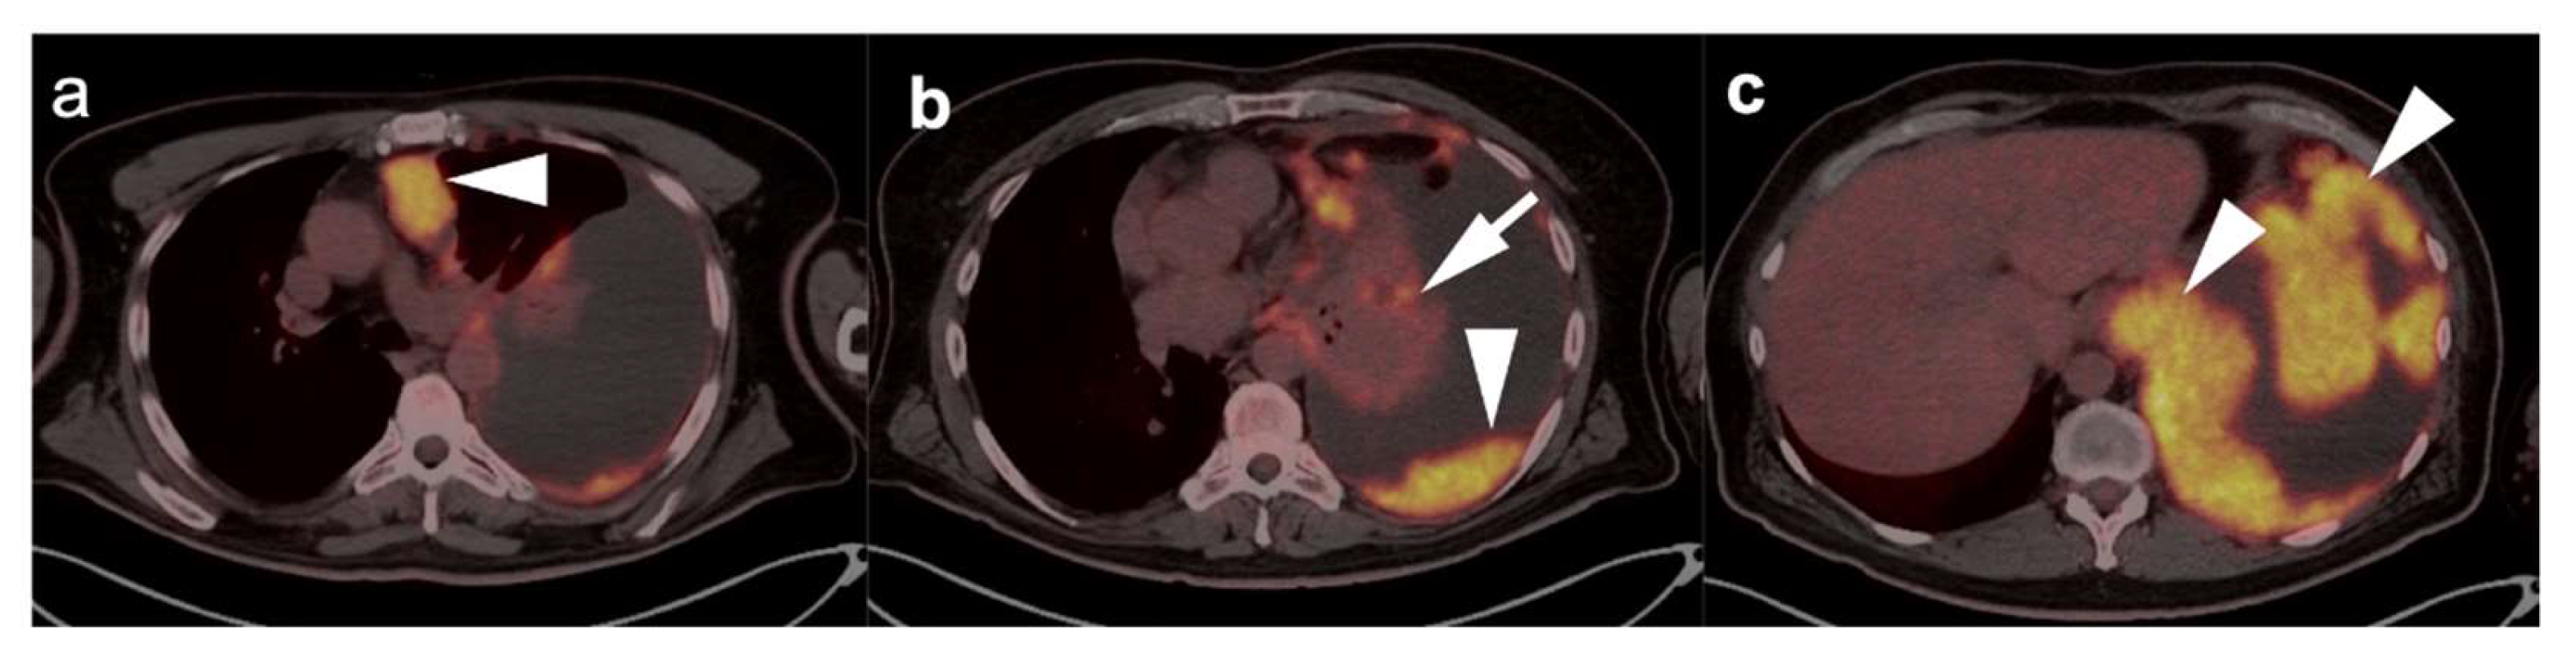

In diagnostic imaging of MPM, FDG PET-CT, whole-body MRI and PET-MRI show superiority over conventional CT [51]. MPM is typically intensely hypermetabolic on FDG PET-CT, making it highly amendable to staging by this method (Figure 13 and Figure 14). Hypermetabolic pleural thickening is typically associated with calcified pleural plaques but can be mimicked by hypermetabolic host inflammatory reaction to talc pleurodesis, empyema, and other pleural inflammatory disease, or by other subpleural malignant processes (Figure 15) [52]. NCCN endorses the use of FDG PET-CT to stage patients only if they are being considered for surgery [53]. However, FDG PET-CT may under-stage mediastinal or nodal disease in MPM and is typically best used for assessment of distant metastases [54]. PET-CT should be done prior to contemplated talc pleurodesis. NCCN also supports the use of FDG PET-CT for mediastinal assessment based on possible evidence of disease progression following induction chemotherapy.

In summary, MPM is typically intensely hypermetabolic on FDG PET-CT, but can be mimicked by hypermetabolic host inflammatory reaction to talc pleurodesis, or other inflammatory or malignant pleural processes. The best use of FDG PET-CT for staging should be reserved for patients considered for surgery or for assessment of suspected disease progression despite induction chemotherapy, with the realization that FDG PET-CT may under-stage mediastinal or nodal disease.